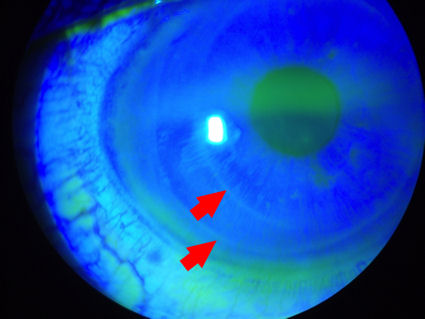

Ниже представлены три фотографии глаза с частично отслоившимся лоскутом LASIK. Пациенту была проведена операция LASIK в 2002 году. Несколько лет спустя на этом глазу сформировалась роговица эктазия , требующий от пациента ношения жестких контактных линз. Из-за незначительной травмы, связанной с контактными линзами, которая для нормального глаза прошла бы без осложнений, лоскут LASIK отделился от роговицы в квадранте с 4:00 до 6:00. Зеленовато-желтый краситель, который был закапан в глаз, проник под лоскут. Этот случай демонстрирует хрупкое состояние роговицы после операции LASIK и доказывает, что лоскут никогда не заживает. (Нажмите на верхнее изображение, чтобы увеличить).

Ниже представлены две фотографии глаза с отслоившимся лоскутом LASIK. Лоскут отслоился во время установки контактных линз - еще один пример того, насколько хрупкой становится роговица после операции LASIK. На первом снимке вы можете отчетливо видеть краситель, который проник в пространство между лоскутом и нижележащей роговицей. Пациенты, перенесшие операцию LASIK, подвергаются пожизненному риску смещения лоскута, инфицирования, врастания эпителия, ДЛК и других осложнений. (Нажмите на фото, чтобы увеличить изображение). На втором изображении красная стрелка указывает на темную область, где лоскут не прикреплен к роговице. Это пространство проходит по краю лоскута.